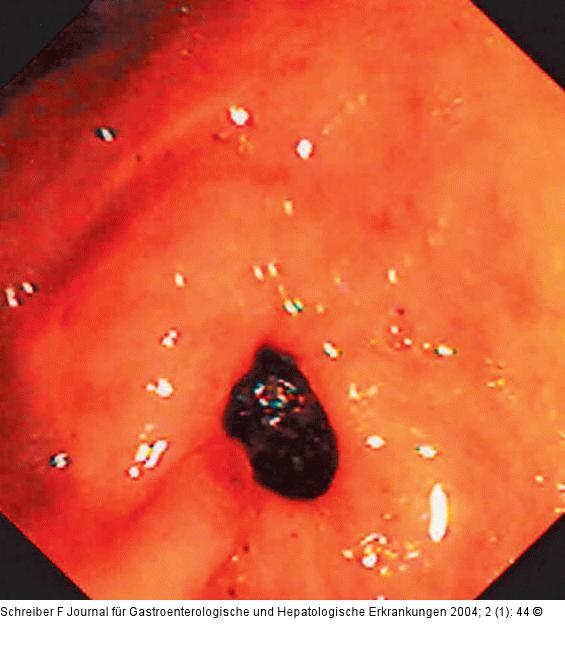

Abbildung 1: Bouveret-Syndrom

Pylorus mit dahinterliegendem Stein